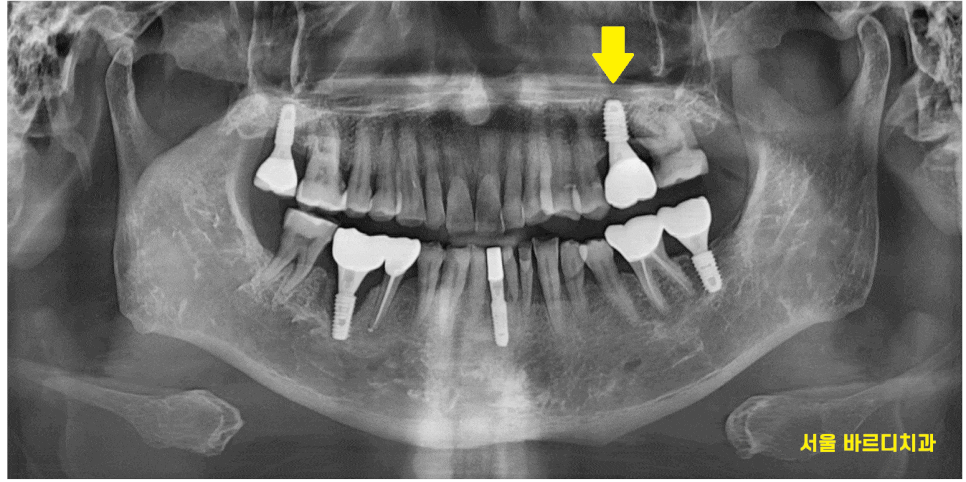

임플란트 시술은 치과에서 가장 큰 치료중 하나입니다.

치아가 상실했을 때 대체하는 치료입니다.

치아 뿌리에 해당하는 부분인데요

임플란트도 잇몸 안쪽 뼈에 식립을 한답니다.

때문에 뼈가 충분할 수록

임플란트 수술과 예후에 좋아요~

뼈가 부족한 부분에 대해서는

추가적으로 이식을 해서 보충을 해주기도 하고요.